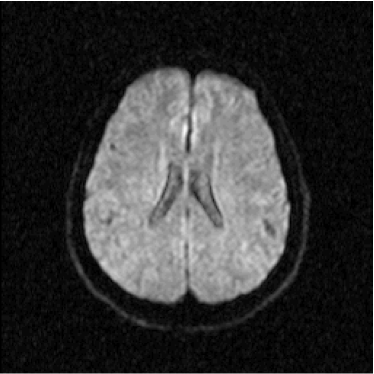

The diffusion-weighted magnetic resonance (MR) images were acquired from the clinical images database of the Laboratory of MR Images, at the Physics Department of Universidade Federal de Pernambuco, Recife, Brazil. The image database is composed by real clinical images acquired from a clinical MR tomographer of 1.5 T. The MR images used in this work corresponds to an unique volunteer with Alzheimer’s. As a case study there were used 80 DW-MR images, corresponding to 4 volumes of 20 axial slices, where one of these volumes is composed by ADC maps. All of these images correspond to a 70-year-old male patient with Alzheimer’s disease, with the following diffusion exponents: 0 s/mm2, 500 s/mm2 and 1000 s/mm2.

Figure 2: Axial DW-MR image of 13th slice with diffusion exponent of 500 s/mm2

Refer to caption

Figure 3: Axial DW-MR image of 13th slice with diffusion exponent of 1000 s/mm2

To perform the training we chose 13th slice of each volume sample (figures 1, 2 and 3), once this slice shows the temporal corni of the lateral ventriculi. The exhibition of such structures facilitates the analysis of the specialist and helps him to find a correlation between data generated by our computational tool and a priori specialist knowledge. Furthermore, slice 13 presents a considerable amount of artifacts out of the cranial region.